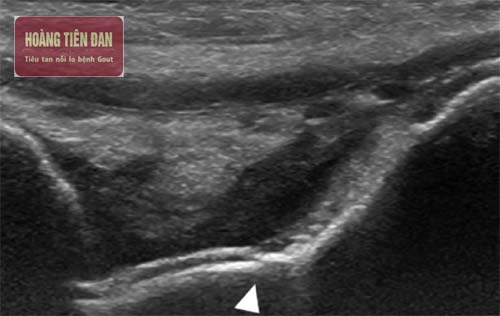

Theo các chuyên gia y tế siêu âm là phương pháp chẩn đoán được sử dụng phổ biến hiện nay để phát hiện ra bất thường và sự thay đổi tại các khớp do bệnh gout gây ra. Nhờ có hình ảnh chụp phim siêu âm sẽ cho thấy rõ triệu chứng viêm khớp của gout, nhờ vào đó bác sỹ cũng có thể dễ dàng phán đoán được bệnh tình của bạn.

Đối với những bệnh nhân siêu âm để chẩn đoán gout chủ yếu là siêu âm sụn khớp cùng các dây chằng ở các vị trí như khớp gối, gân gót chân, mắt cá chân, gân gót và cả khớp bàn ngón chân cái. Người bị gout sẽ nhận thấy bất thường rõ rệt của các gai xương, hiển thị vị trí của các vùng xương bị ăn mòn, thậm chí xuất hiện cả viêm bao hoạt dịch giữa.

Một điểm khác biệt duy nhất giữa người bị bệnh gout thực sự và người bị gout chưa có triệu chứng đó là trên siêu âm sẽ có biểu hiện “dấu viền đôi”. Hình ảnh trên siêu âm cho thấy có 2 đường, một đường là dải echo dài bề mặt không đều do các tinh thể muối urat lắng đọng trên bề mặt sụn khớp, còn đường thứ hai đó là viền vỏ xương có echo dày.